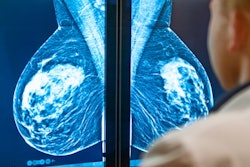

Abnormal mammogram (left) compared with normal mammogram. Image courtesy of the RSNA.